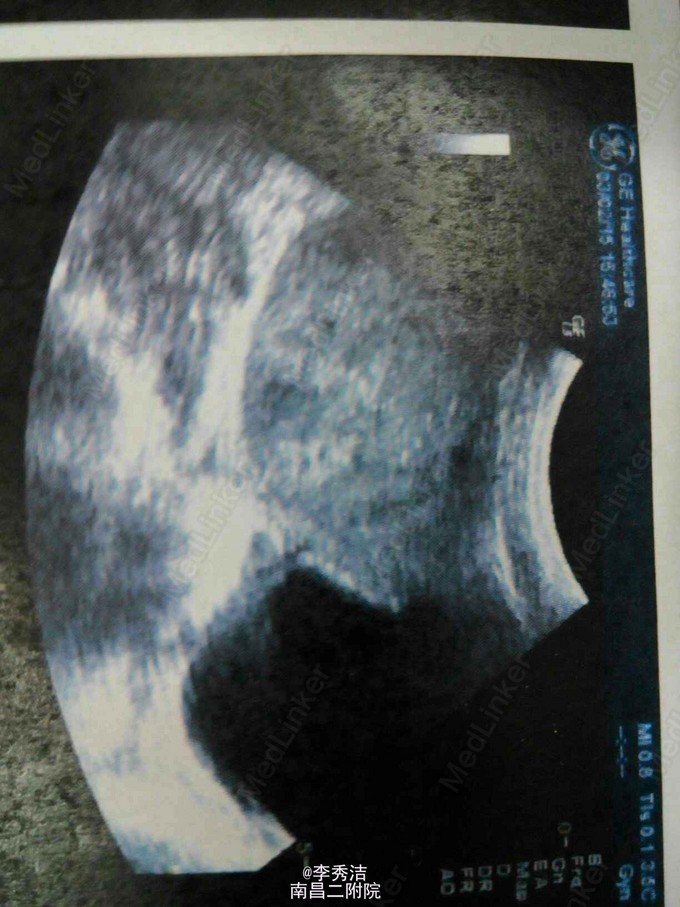

患者,女,10岁,因“反复右下腹痛4天,发现盆腔包块4天”入院,彩超检查示幼稚子宫,右侧盆腔10*10*9cm肿物,择日腹腔镜手术,术中见右侧卵巢肿瘤大小约10*10*9cm肿物,表面见一长约3cm破裂口,囊内液黄色烂肉状。术中冰冻切片示卵巢囊瘤。